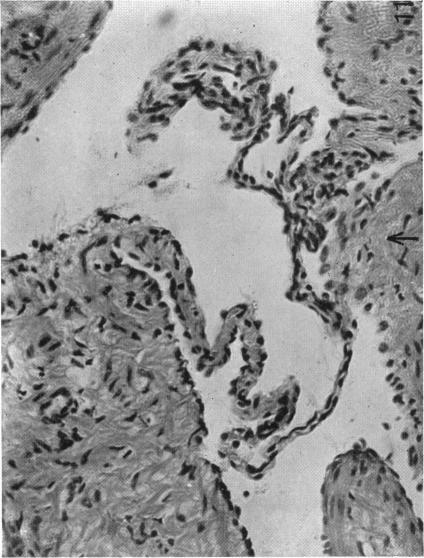

The So-called Interscapular Gland and Tumours Arising Therein.